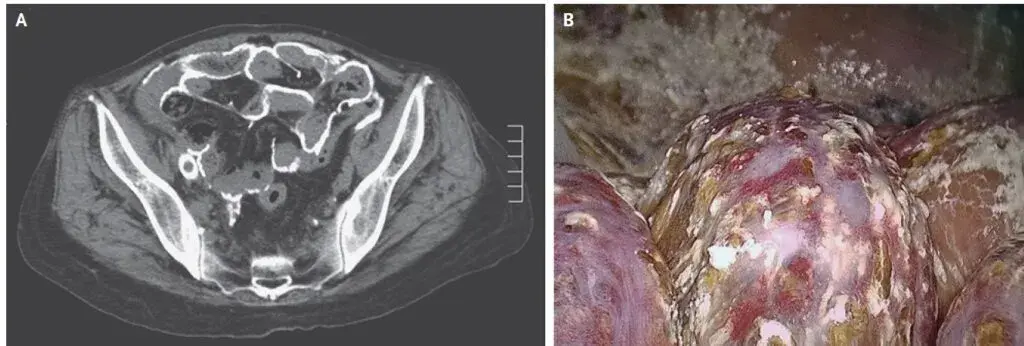

Líquido peritoneal com sangue?